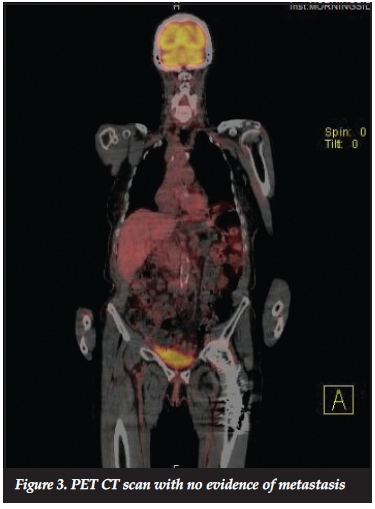

No bony involvement was evident on plain radiographs (Figure 2). A PET CT scan (Figure 3) showed no metastases.